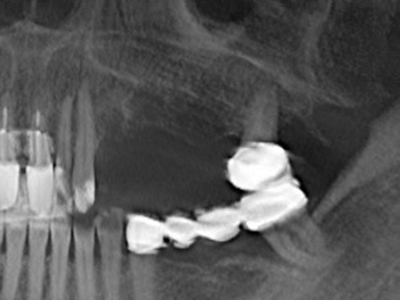

Indication: Preparation near nerves

As noted above, indications for piezosurgery can also be found in the field of conservative dental surgery. Special working tips simplify the exposure of root tips and make it easier to protect nerves and sinus mucous membranes, particularly in the lower premolar and upper posterior tooth regions. Angled diamond tips are used to precisely prepare the resection cavity for the retrograde root filler material for unsealed apical obturation. The ultrasonic technology means the tips can be very slender, which improves the view and the size of the access cavity. As a result, the application of ultrasonic surgery for this indication is one of the standard procedures for apical resection (Del Fabbro, Tsesis et al. 2010, Scarano, Artese et al. 2012).

Indication: Apical resection

When surgical procedures are performed on bone in the immediate vicinity of sensitive structures such as blood vessels or nerves, rotary instruments pose a significant risk of iatrogenic injury. Piezoelectric devices can be helpful for preparation of bone covers and removal of hard tissue close to nerves, particularly for exposure of nerves after iatrogenic injury but also during nerve lateralization for resective and reconstructive procedures or implant placement (Fig. 17-20). Light contact between the piezotip and the nerve does not generally result in damage but proceeding incautiously with saw-like motions or attachments where a residual bone substrate remains may cause temporary or even permanent nerve damage. However, the risk of damage is considered to be substantially lower than when using saws or milling instruments (Pereira, Gealh et al. 2014).